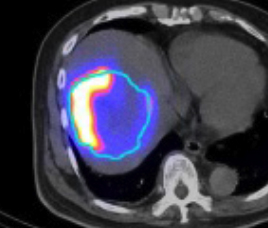

- 钇90选择性内部放射治疗

- 使用鍀99m MAA(左)模拟钇90粒子分布(右)

- 评估治疗可行性

- 由双示踪剂正电子/电脑双融扫描计算处方剂量

- 用正电子/电脑双融扫描显示钇90粒子分布(右)

99mTc MAA SPECT/CT Y-90 PET/CT